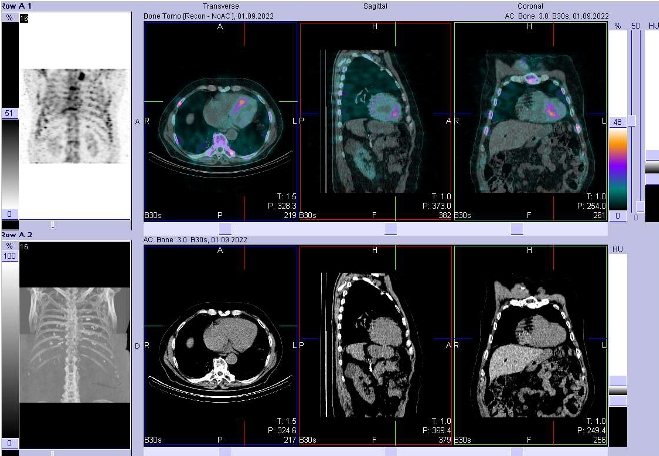

/ Obr. č. 2: Fúze obrazů SPECT a CT. Zaměřeno na levou srdeční komoru.

/ Obr. č. 3: Fúze obrazů SPECT a CT. Zaměřeno na levou srdeční komoru.

Pozorujeme vyšší akumulaci radiofarmaka v hrudní a bederní páteři, pravém sternoklavikulárním skloubení, levém kolenním kloubu, pravém nártu, pravém ramenním a loketním kloubu, také však v myokardu.

Závěr: zvýšená osteoblastická aktivita v hrudní a bederní páteři, pravém sternoklavikulárním skloubení, levém kolenním kloubu, pravém nártu, pravém ramenním a loketním kloubu, také však v myokardu. Nález svědčí pro degenerativní, případně zánětlivé změny. Dále se pravděpodobně také jedná o transthyretinovou srdeční amyloidózu – vhodné došetření u nás s radiofarmakem

99mTc-DPD – po telefonickém objednání.

V uvedeném případě kostní scintigrafie pořízené pomocí hybridní kamery SPECT/CT je suspektní nález srdeční amyloidózy.